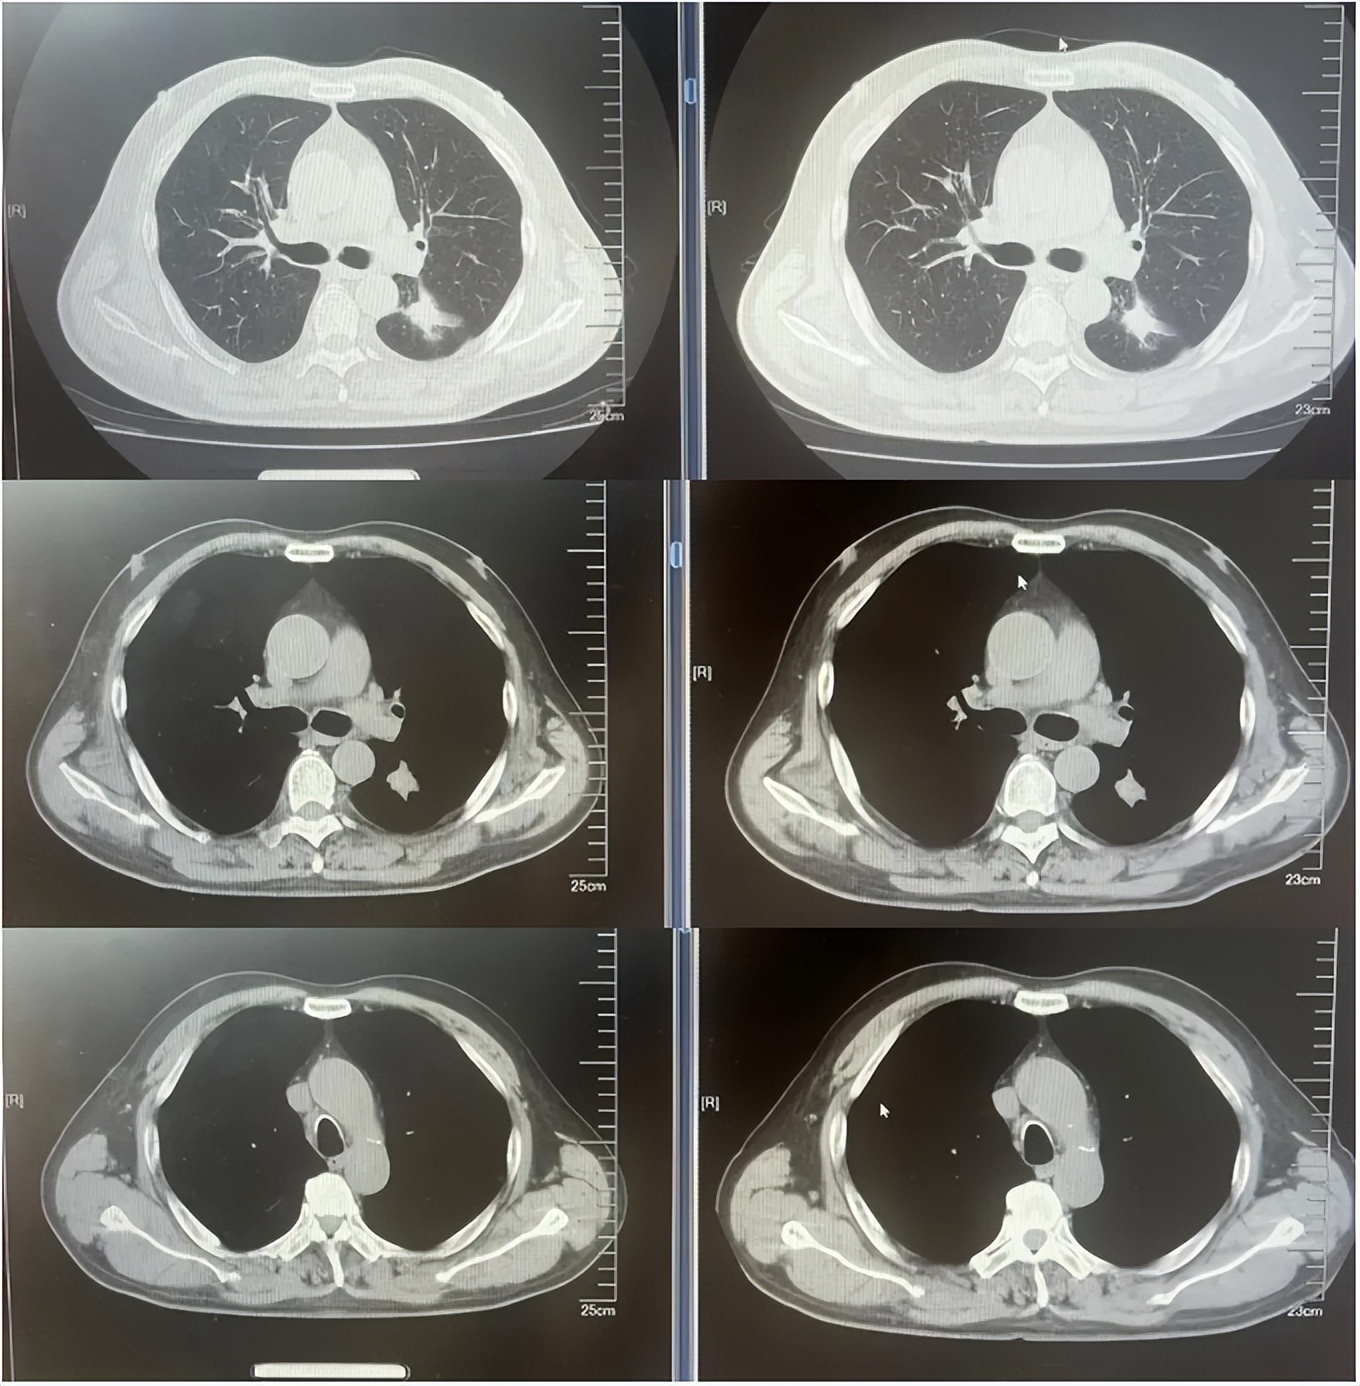

德曲妥珠单抗治疗4周期(2025.5)疗效对比

德曲妥珠单抗治疗6周期(2025.7)疗效对比

德曲妥珠单抗治疗4周期(2025.4)疗效对比